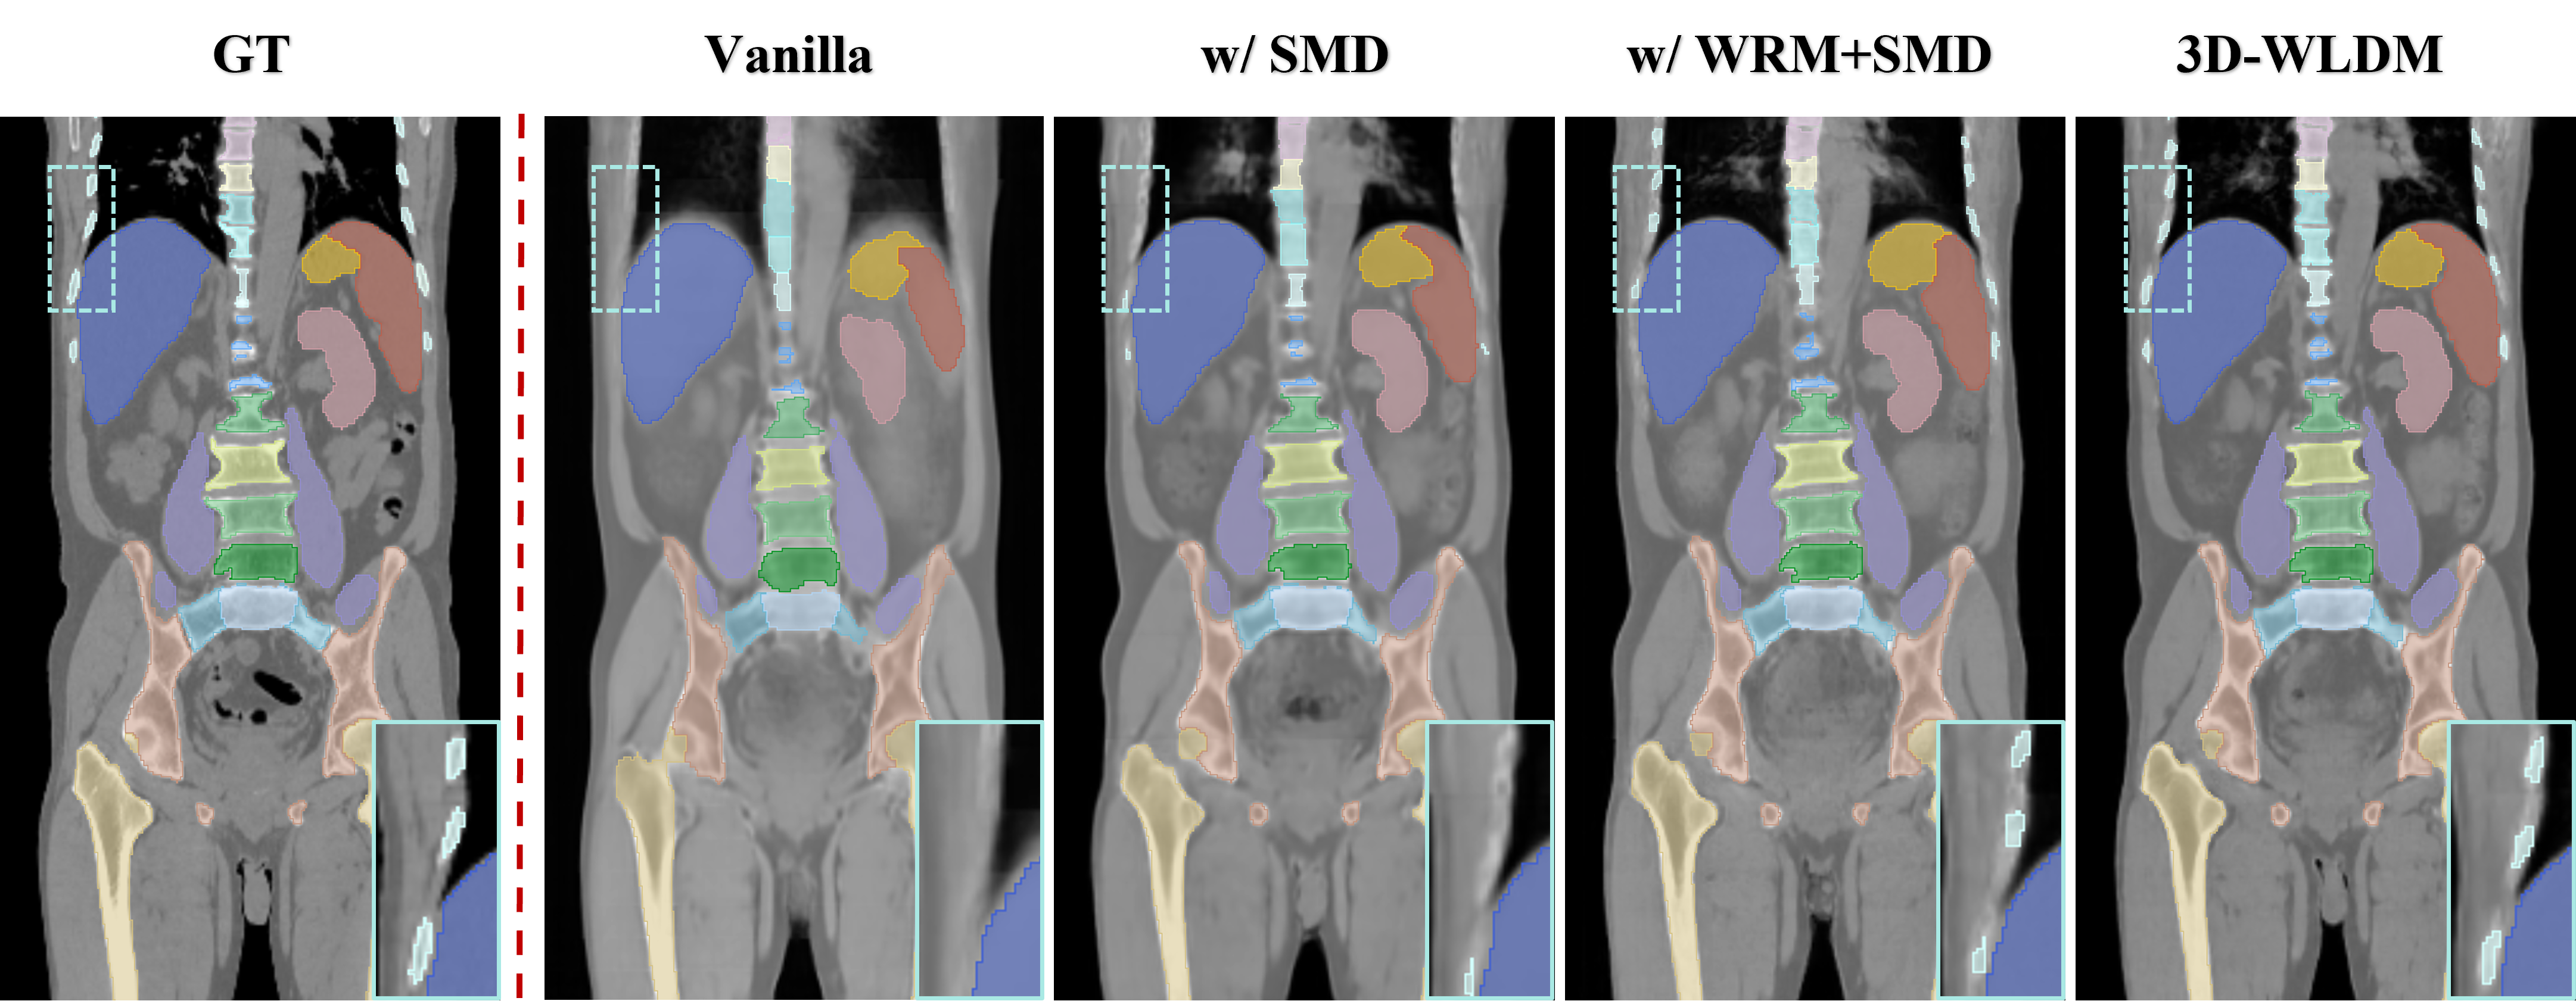

We performed MR-to-CT modality translation experiments to benchmark the proposed 3D Wavelet Latent Diffusion Model (3D-WLDM) against several state-of-the-art baselines, including DDPM [41], DDIM [39], StableDiffusion 2D (StableDM-2D)[37], ControlNet[34], StableDiffusion 3D (StableDM-3D)[37], and CycleGAN[42]. Representative qualitative comparisons are illustrated in Fig. 5.

In contrast, our proposed 3D-WLDM demonstrates marked improvements in both visual fidelity and anatomical coherence. The integration of Wavelet Blocks enhances multiscale encoding and reconstruction, while the Structure-Modality Disentanglement module mitigates inconsistencies in latent space representation. Furthermore, the DSCA module significantly improves the generation of fine structural details during the diffusion process. Together, these components enable 3D-WLDM to produce CT reconstructions that are not only visually compelling but also structurally faithful to the underlying anatomy.

These quantitative findings are further supported by the qualitative results in Fig.7. The Vanilla model generates synthetic CT images with perceptual quality comparable to StableDM-3D (Fig.5), yet fails to capture modality-specific transformations with sufficient structural fidelity, particularly in anatomically complex 3D regions where spatial encoding is inherently more challenging.

Introducing SMD leads to more accurate anatomical alignment by explicitly preserving structure throughout the diffusion process. Organ and tissue boundaries become more coherent, though finer anatomical details remain underrepresented. The addition of WRM markedly improves the synthesis of high-frequency features, especially in regions with intricate bone morphology such as the vertebrae and ribs, by leveraging wavelet-domain encoding to reinforce multiscale structural representation.

The full model further benefits from the integration of DSCA, which refines the fusion of structural and modality cues and enhances both generation stability and contrast accuracy. As shown in Fig. 7, this results in improved delineation of abdominal organs, such as the stomach and kidneys, with sharper boundaries and more realistic texture.